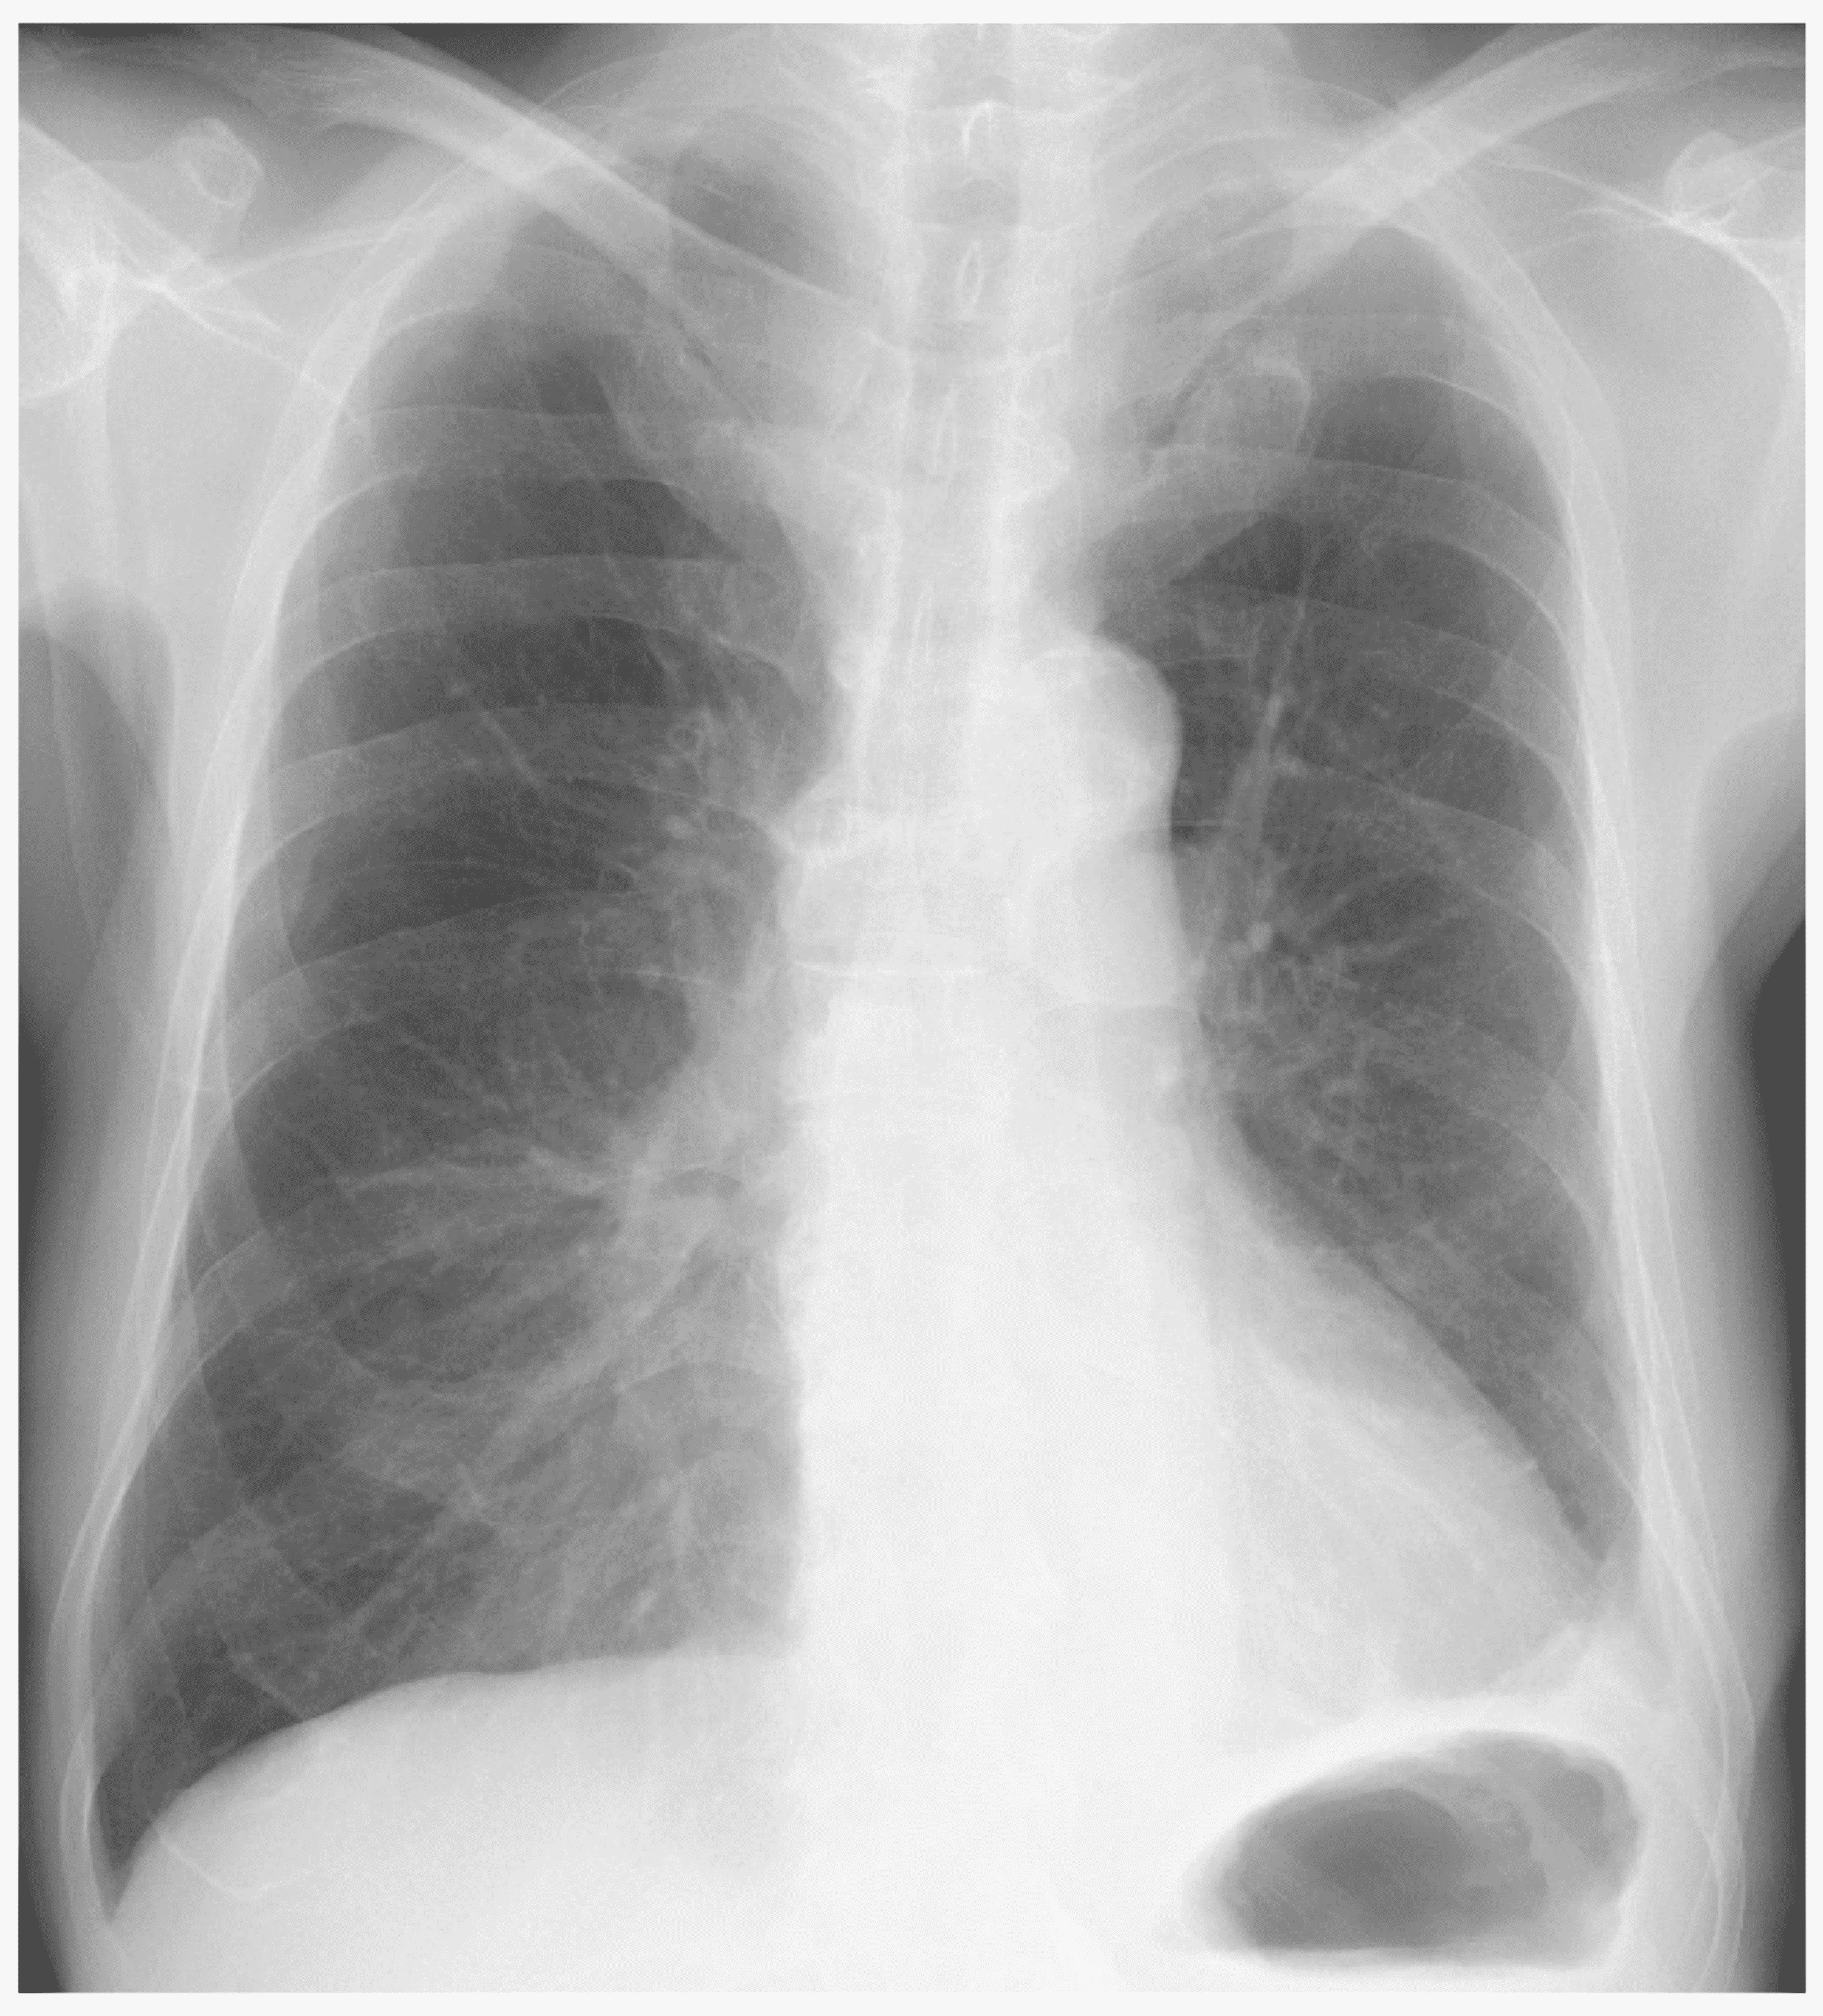

A chest Xray revealing proper placement of chest tubes with a moderate How Long Is A Chest Tube Surgery The duration for which a chest tube is needed varies but is usually a few days. According to the chest foundation, most people need to keep the chest tube in for a few days. When removing a chest tube, a doctor will cut. Keep your incision covered with a bandage for 48. Chest tube insertion (also called tube thoracostomy) is. How Long Is A Chest Tube Surgery.